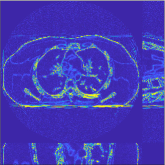

This section compares the generalization capabilities between the proposed MBIR method, PWLS-ST-, and a denoising deep NN, FBPConvNet [14], that are trained from the phantom data; in particular, we tested the trained PWLS-ST- and FBPConvNet models to phantom and clinical scan data. The results in Fig. 6 show that the non-MBIR FBPConvNet method has higher overfitting risks, compared to the proposed PWLS-ST- MBIR method. When tested on clinical scan data, PWLS-ST- achieves much more accurate reconstruction, compared to FBPConvNet. See Fig. 6(b). When tested on phantom data, FBPConvNet generates more unnatural features as the number of views reduces, although it gives lower RMSE values compared to PWLS-ST-. See zoom-ins in Fig. 6(a). The FBPConvNet results above correspond to those in the recent work [16] that FBPConvNet [14] generated some unexpected structures.

Researchers have applied (deep) neural networks (NNs) to sparse-view and low-dose CT reconstruction problems. Early works focused on image denoising [11, 12, 13, 14, 15] using the good mapping capabilities of deep NNs. However, the greater mapping capability can increase the chance of causing some artificial features when test images are not similar to training images. (See Fig. 6.) More recent works combined image mapping NNs with model-based image reconstruction (MBIR) frameworks that consider CT physics [16, 17, 18, 19, 20]. However, for general image mapping NNs, it is difficult to explicitly write the corresponding optimization problems within an MBIR framework. Without explicit cost functions, it is challenging to guarantee the non-expansiveness (or -Lipschitz continuity) of the image mapping NNs and obtain “optimal” and convergent image reconstruction, especially when the mapping NNs are identical across iterations [19]. In addition, considering that the methods are trained with supervised learning, one would expect optimal results by using pairs of “noiseless” and “noisy” images in the training processes. In practice, however, it is challenging to obtain noiseless images to construct such paired training dataset in CT imaging. Based on a recent “Noise2Noise” training method [21], some recent works [22, 23] show that training image mapping NNs with pairs of noisy images could provide satisfactory image quality in certain applications. However, training with noisy images has certain limitations in sparse-view CT reconstruction (see Section S.I in the supplement).